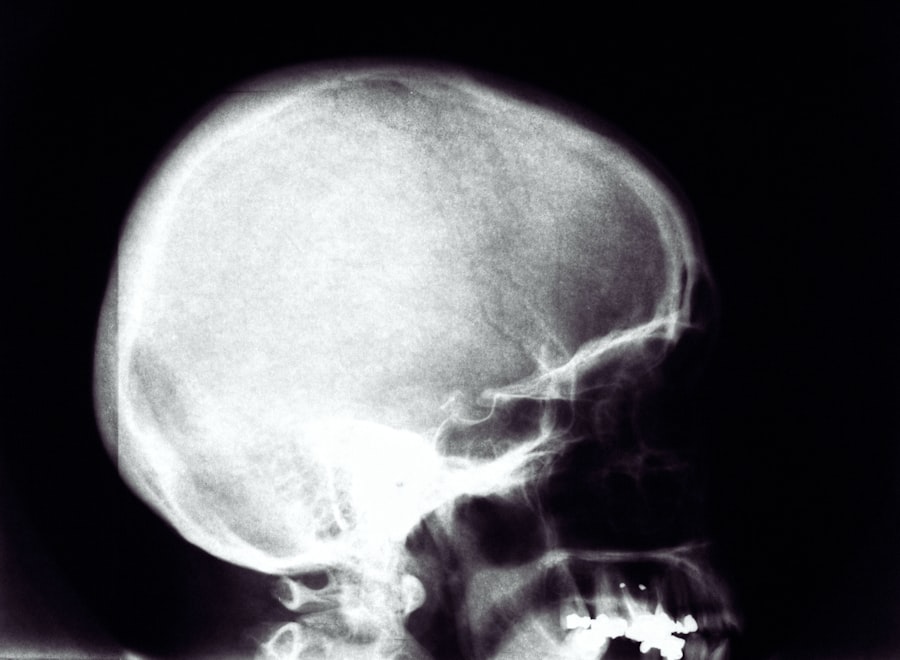

When X-rays pass through the body, they are absorbed at different rates by different tissues. Dense materials like bones absorb more X-rays and appear white on the resulting image, while softer tissues allow more X-rays to pass through and appear darker. This contrast creates a detailed image that can help healthcare professionals identify abnormalities or injuries. The entire process is quick, often taking just a few seconds, making it a convenient option for both patients and medical staff.

X-rays play a pivotal role in diagnosing various diseases and conditions across multiple medical specialties. In orthopedics, they are essential for identifying fractures, dislocations, and degenerative joint diseases like arthritis. By providing clear images of bone structures, X-rays enable orthopedic surgeons to make informed decisions regarding treatment options.

In addition to musculoskeletal issues, X-rays are crucial in detecting diseases affecting internal organs. For example, chest X-rays are commonly used to identify conditions such as pneumonia, heart failure, or lung cancer. By visualizing the lungs and surrounding structures, healthcare providers can assess the severity of these conditions and determine appropriate interventions. This diagnostic capability underscores the importance of X-rays in comprehensive patient care.